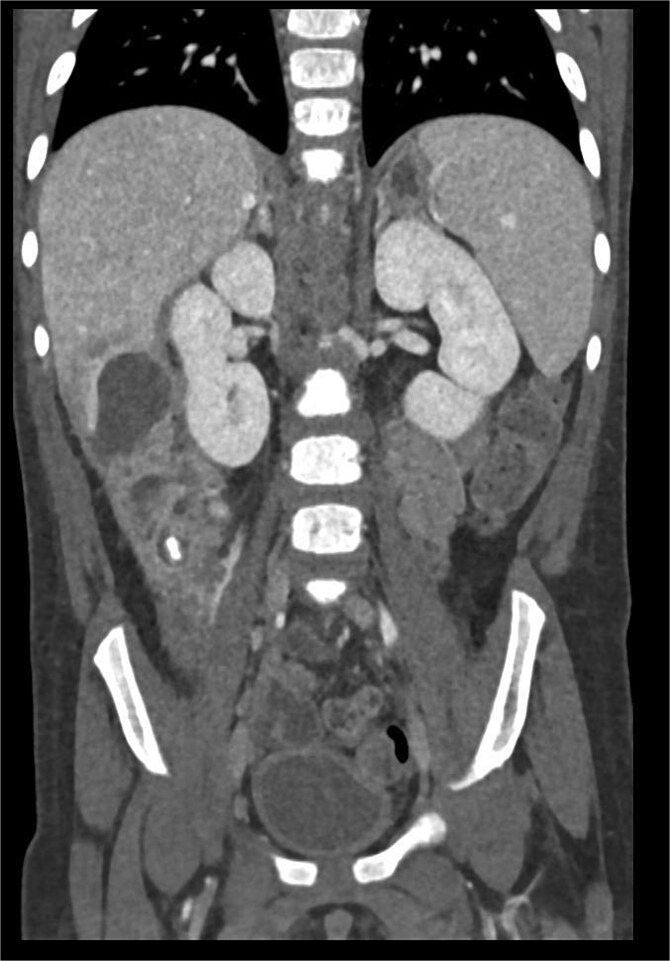

摘要肝下脓肿是急性阑尾炎的罕见并发症,常因诊断迟缓及表现不典型而引起。我们报告的情况下,一个3岁的男性表现发烧和腹痛,后来诊断为肝下脓肿继发于急性阑尾炎。腹部影像学显示多发脓肿,包括原发性肝下脓肿邻近肝V节和肝VI节,盲肠后炎性阑尾伴阑尾炎。患者接受抗生素治疗,开腹,引流肝下脓肿,切除坏疽阑尾。手术探查发现炎性粘连累及十二指肠和邻近的肠道结构,我们对其进行了精心的解剖和处理。这个病例强调了高度临床怀疑和及时成像的重要性,儿科患者急性阑尾炎的不典型表现。

Subhepatic abscesses are rare complications of acute appendicitis, often caused by delayed diagnosis and atypical presentation. We report the case of a 3-year-old male presenting with fever and abdominal pain, later diagnosed with a subhepatic abscess secondary to acute appendicitis. Abdominal imaging revealed multiple abscesses, including a primary subhepatic abscess adjacent to liver segments V and VI, and a retrocecal inflamed appendix with an appendicolith. The patient was treated with antibiotics and underwent laparotomy, drainage of the subhepatic abscess, and removal of a gangrenous appendix. Surgical exploration revealed inflammatory adhesions involving the duodenum and adjacent intestinal structures, which were meticulously dissected and managed. This case underscores the importance of high clinical suspicion and timely imaging in pediatric patients with atypical presentations of acute appendicitis.